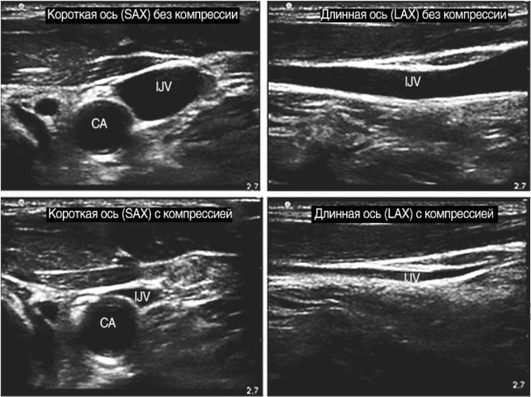

ОСНОВНЫЕ ПОЛОЖЕНИЯ Выбор доступа

В соответствии с приказом Минздрава России от 23.07.2010 №541н «Об утверждении единого квалификационного справочника должностей руководителей, специалистов и служащих», врач анестезиолог-реаниматолог определяет показания и производит катетеризацию центральных вен. При выборе внутривенного доступа, типа катетера и количества просветов в нем врач, устанавливающий ЦВК, учитывает характер заболевания, анатомическую область места доступа, длительность и интенсивность терапии, риски осложнений, включая инфекционные и иные индивидуальные особенности пациента.